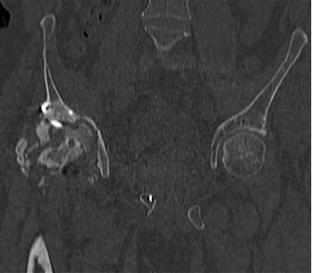

Пациент 49 лет, паровозная травма 23.2.2006, получил вертикальная нестабильное повреждение таза, разрыв левого крестцово-подвздошного сочленения, перелом лонной, седалищной костей слева, T-образный оскольчатый перелом правой вертлужной впадины с переломом заднего края, вывих правого бедра, посттравматическая пояснично-крестцовая плексопатия с обеих сторон, паралич мышц правой голени. В день травмы - вправление вывиха, скелетное вытяжение, 14.3.2006 чрескостный остеосинтез таза. 20.4.2006 остеосинтез правой вертлужной впадины пластинами, осложнившийся нагноением межмышечной гематомы правой ягодичной области. Получал консервативное лечение, было достигнуто полное заживление раны. 24.7.2006 введены илиосакральные винты слева. С декабря 2006 года и по настоящее время ходит на костылях без опоры на правую ногу. Планируется THA. Помогите определиться с вариантом костной пластики? И какую укрепляющую конструкцию использовать?